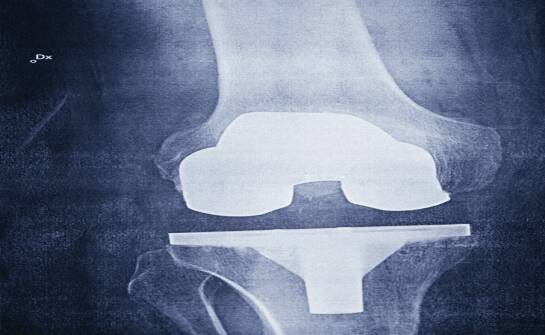

Endoproteza stawu biodrowego — co warto wiedzieć przed decyzją operacyjną

„Czy to już ten moment, żeby zdecydować się na operację?” – to jedno z najczęstszych pytań, jakie pada w gabinetach ortopedycznych, gdy ból biodra przestaje być epizodem, a zaczyna wyznaczać rytm dnia. Jeśli łapiesz się na tym, że planujesz trasę po mieszkaniu tak, żeby było mniej kroków, rezygnujes